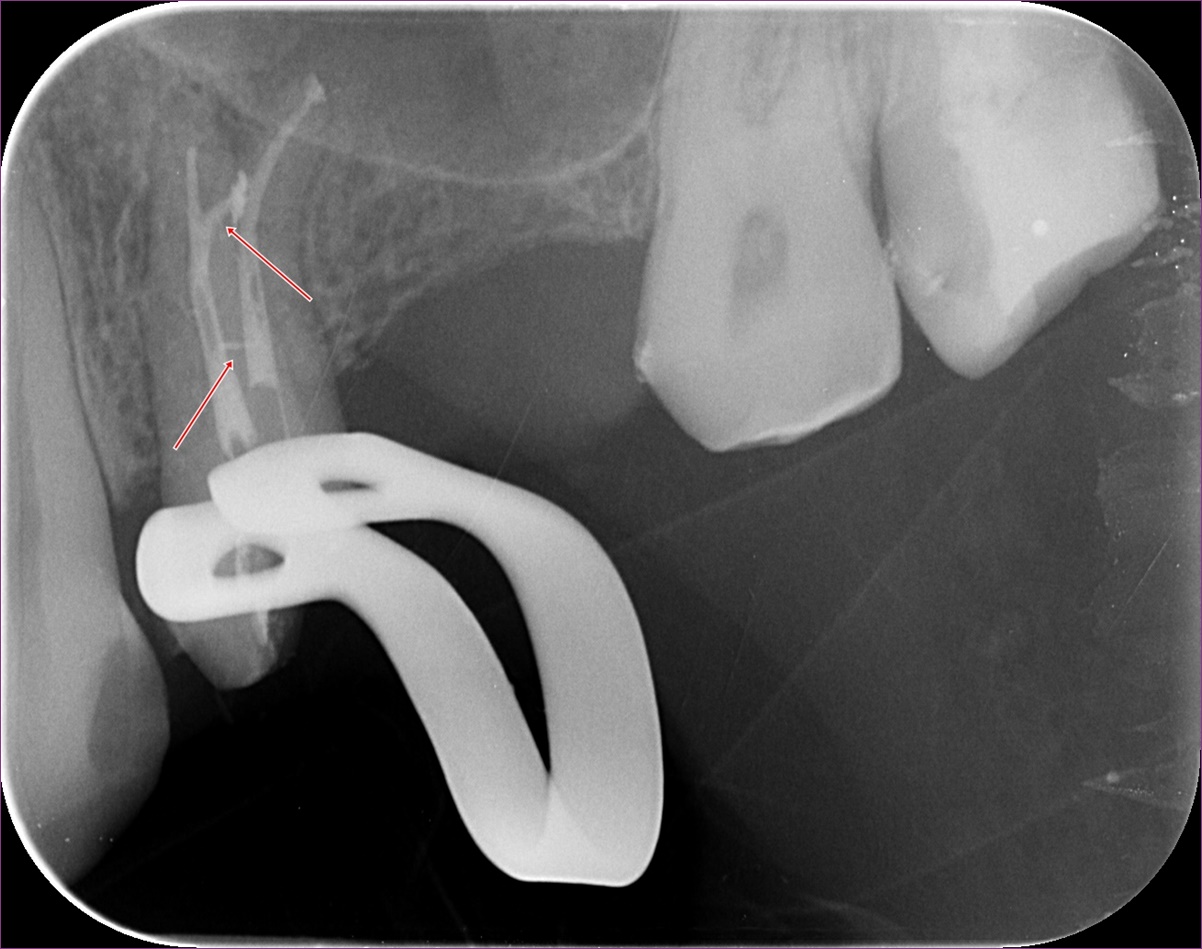

A fog kinyitása után a csatornákat a látható görbület miatt óvatosan, különleges technikával dolgoztuk fel. Már a kezelés elején érzékelhető volt, hogy a két, egyébként külön kijárattal rendelkező csatorna között van kapcsolat. Az egyik csatornába egy speciális szívóberendezést helyezve a másik csatornából is sikerült eltüntetni a folyadékot. Közvetlenül a gyökértömés előtt a majdani gyökértömő „pálcikákkal” készült röntgenfelvételen ellenőriztük, valóban jó helyen vagyunk-e, és az elektromos bemérő készülékünk segítségével jó hosszokat sikerült-e megállapítanunk. A felvételen egyenesebbnek látszó gyökérben rövidebbnek tűnik a hossz a röntgenen látható véghez képest, azonban itt nem a gyökércsúcson van a kijárat, hanem a gyökér oldalán.

Mint minden alkalommal, a gyökértömés megkezdése előtt a fog csatornarendszerét többféle vegyszerrel, illetve egy speciális átöblítő rendszerrel kezeltük, hogy a benne lévő idegszövet-maradványokat teljes mértékben el tudjuk távolítani. Erre azért van szükség, mert az úgynevezett oldalcsatornákat mechanikusan, gyökérkezelő tűkkel nem tudjuk közvetlenül elérni. A gyökértömésről készült felvételen nagyszerűen látszik egy ilyen oldalcsatorna teljes feltelítődése: ezt nyilakkal jelöltük.